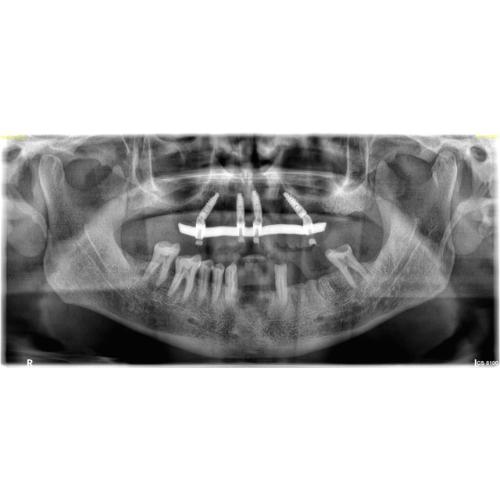

Dental implants in Kishangarh have transformed the field of restorative dentistry, offering a robust and long-lasting alternative to traditional tooth replacement methods. They are considered the gold standard for restoring missing teeth because they function and feel just like natural teeth. At its core, a dental implant is a small, screw-shaped post, typically made of titanium, that is surgically placed into the jawbone. This post acts as a replacement for the tooth’s root, providing a stable foundation for a custom-made crown.

The success of a dental implant lies in a process called osseointegration. This is where the implant post fuses directly with the jawbone over several months. This fusion is critical because it creates a strong, durable anchor that can withstand the forces of chewing and biting. Once osseointegration is complete, a small connector piece called an abutment is attached to the implant, and finally, a lifelike crown is placed on top. The result is a seamless and functional tooth that restores your smile and your ability to eat and speak with confidence in Kishangarh.

All-on-4 Technology

All-on-4 uses four strategically positioned implants—two straight in front and two angled in back—to support a fixed full-arch bridge. It maximizes available bone, often avoids grafting, and can provide a provisional set of teeth the same day, helping Kishangarh patients transition from dentures or failing teeth to a confident, functional smile.